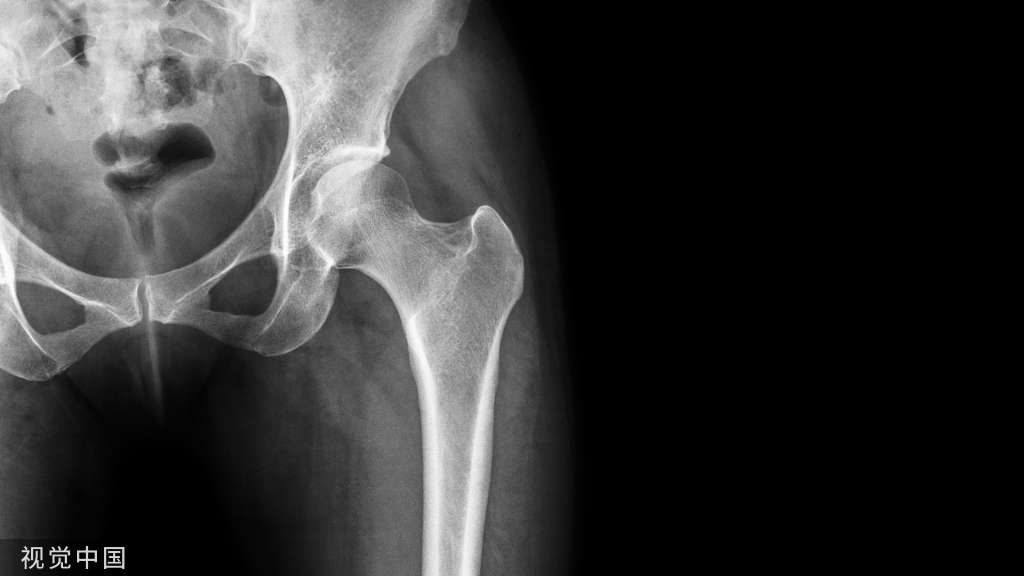

(A-C)术前X光显示左侧股骨近端骨量减少,翻修时预先放置的模块化骨干接合股骨柄用于假体周围骨折的治疗。(D和E)在外展肌重建前进行的MRI图像显示臀中肌和小肌脂肪萎缩,股骨肌腱附着处改变。(F和G)外展肌重建18个月后的部分MRI图像显示臀中肌附着完整,臀小肌部分连续。患者报告的外展肌重建术23个月的结果包括:静息疼痛,1/10;行走疼痛,3/10;Harris髋关节评分,61;牛津髋关节评分,22。患者报告中度跛行,仅需长时间步行时需要拐杖。

(A-C)术前X光显示大转子有轻微骨折,和先前植入的右全髋关节假体,包括非骨水泥的股骨柄和非骨水泥的髋臼假体。(D和E)在外展肌重建前进行的MRI图像显示臀中肌腱仍然附着在大转子骨折片段上。这块骨折碎片已经移位,近端移位。臀小肌腱终止于股骨近端的软组织。外展肌重建术后18个月的报告包括:休息疼痛,3/10;行走疼痛,8/10;Harris髋关节评分,26;牛津髋关节评分,37。患者报告中度跛行,行走时使用助行器。

(A-C)术前X光显示先前植入的右侧全髋关节假体,包括非骨水泥的股骨柄和非骨水泥的髋臼假体。(D和E)外展肌重建后12个月MRI图像显示臀中肌、臀小肌、臀大重建瓣和阔筋膜张肌重建瓣完整。患者报告的外展肌重建术22个月的结果包括:静息疼痛,1/10;行走疼痛,3/10;Harris髋关节评分,58;牛津髋关节评分,23。病人报告说,走路时有轻微的跛行和拐杖。